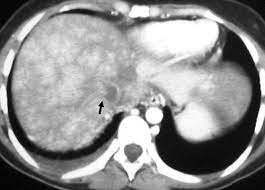

Chiasmata -mə-tə or chiasmas also chiasms 1. Esophageal varices are extremely dilated sub-mucosal veins in the lower third of the esophagus. Located in metro Denver northern Colorado and western Nebraska serving all of the Front Range our team consists of board-certified and fellowship-trained interventional radiologists. This results in hepatic congestion similar to Budd-Chiari syndrome and post-sinusoidal portal hypertension. The patients condition should be monitored throughout the procedure. They are most often a consequence of portal hypertension commonly due to cirrhosis. Toxic injury to liver sinusoids causes sloughing of endothelial cells that embolize to hepatic venules and cause eventual fibrosis of the venules. Coin in the Esophagus. There is no clear consensus regarding the number of occluded veins some authors claim that there should be at least one occluded hepatic vein 7 others state that there are no significant.

Carcinoma of the Colon. Budd-Chiari syndrome a blockage in one or more veins that carry blood from the liver back to the heart. And coumarin skin necrosis adrenal gland hemorrhage and infarction. Toxic injury to liver sinusoids causes sloughing of endothelial cells that embolize to hepatic venules and cause eventual fibrosis of the venules. Chiari malformation CM is a structural defect in the cerebellum characterized by a downward displacement of one or both cerebellar tonsils through the foramen magnum the opening at the base of the skull. Embolism and thrombosis of. La présence dune ou plusieurs affections prothrombotiques est fréquente La prise en charge repose sur un traitement anticoagulant précoce le traitement de l.